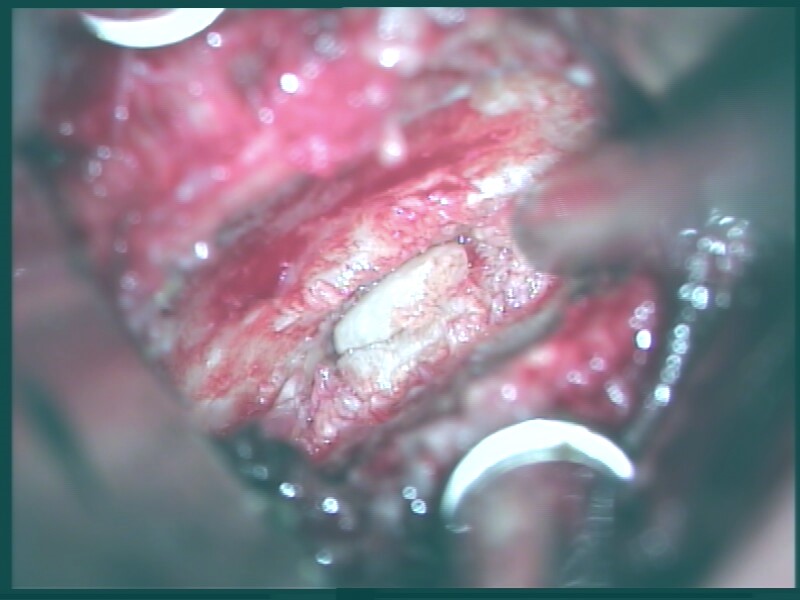

Bei der Operation, welche unter Vollnarkose durchgeführt wird, wird ein ca. 4 cm langer, kleiner Schnitt im Bereich der rechten Halsseite angelegt und die Wirbelsäule dargestellt. Unter dem Operationsmikroskop wird die Bandscheibe ausgeräumt und vorhandene knöcherne Einengungen mit Diamantfräsen und feinen, speziellen Stanzen abgetragen. Danach wird die Bandscheibe durch einen Kunststoff- (PEEK) Cage oder ein Titan-Implantat versteift. In speziellen Fällen kann eine Bandscheibenprothese Anwendung finden.

Der Eingriff wird in Vollnarkose und Bauchlagerung mit Überstreckung von Kopf- und Halswirbelsäule durchgeführt. Nach sorgfältigem Ablösen der sehr kräftigen Nackenmuskulatur von den hinteren Anteilen der Halswirbelsäule wird unter Röntgenkontrolle die richtige Etage verifiziert. Anschließend werden von hinten mit Mikrofräsen und Stanzen die aneinander grenzenden seitlichen Anteile der Wirbelhalbbögen entfernt. Der geschaffene, knöcherne Defekt ist in aller Regel kleiner als ein Fingernagel und verhilft dem Patienten zur Beschwerdefreiheit.